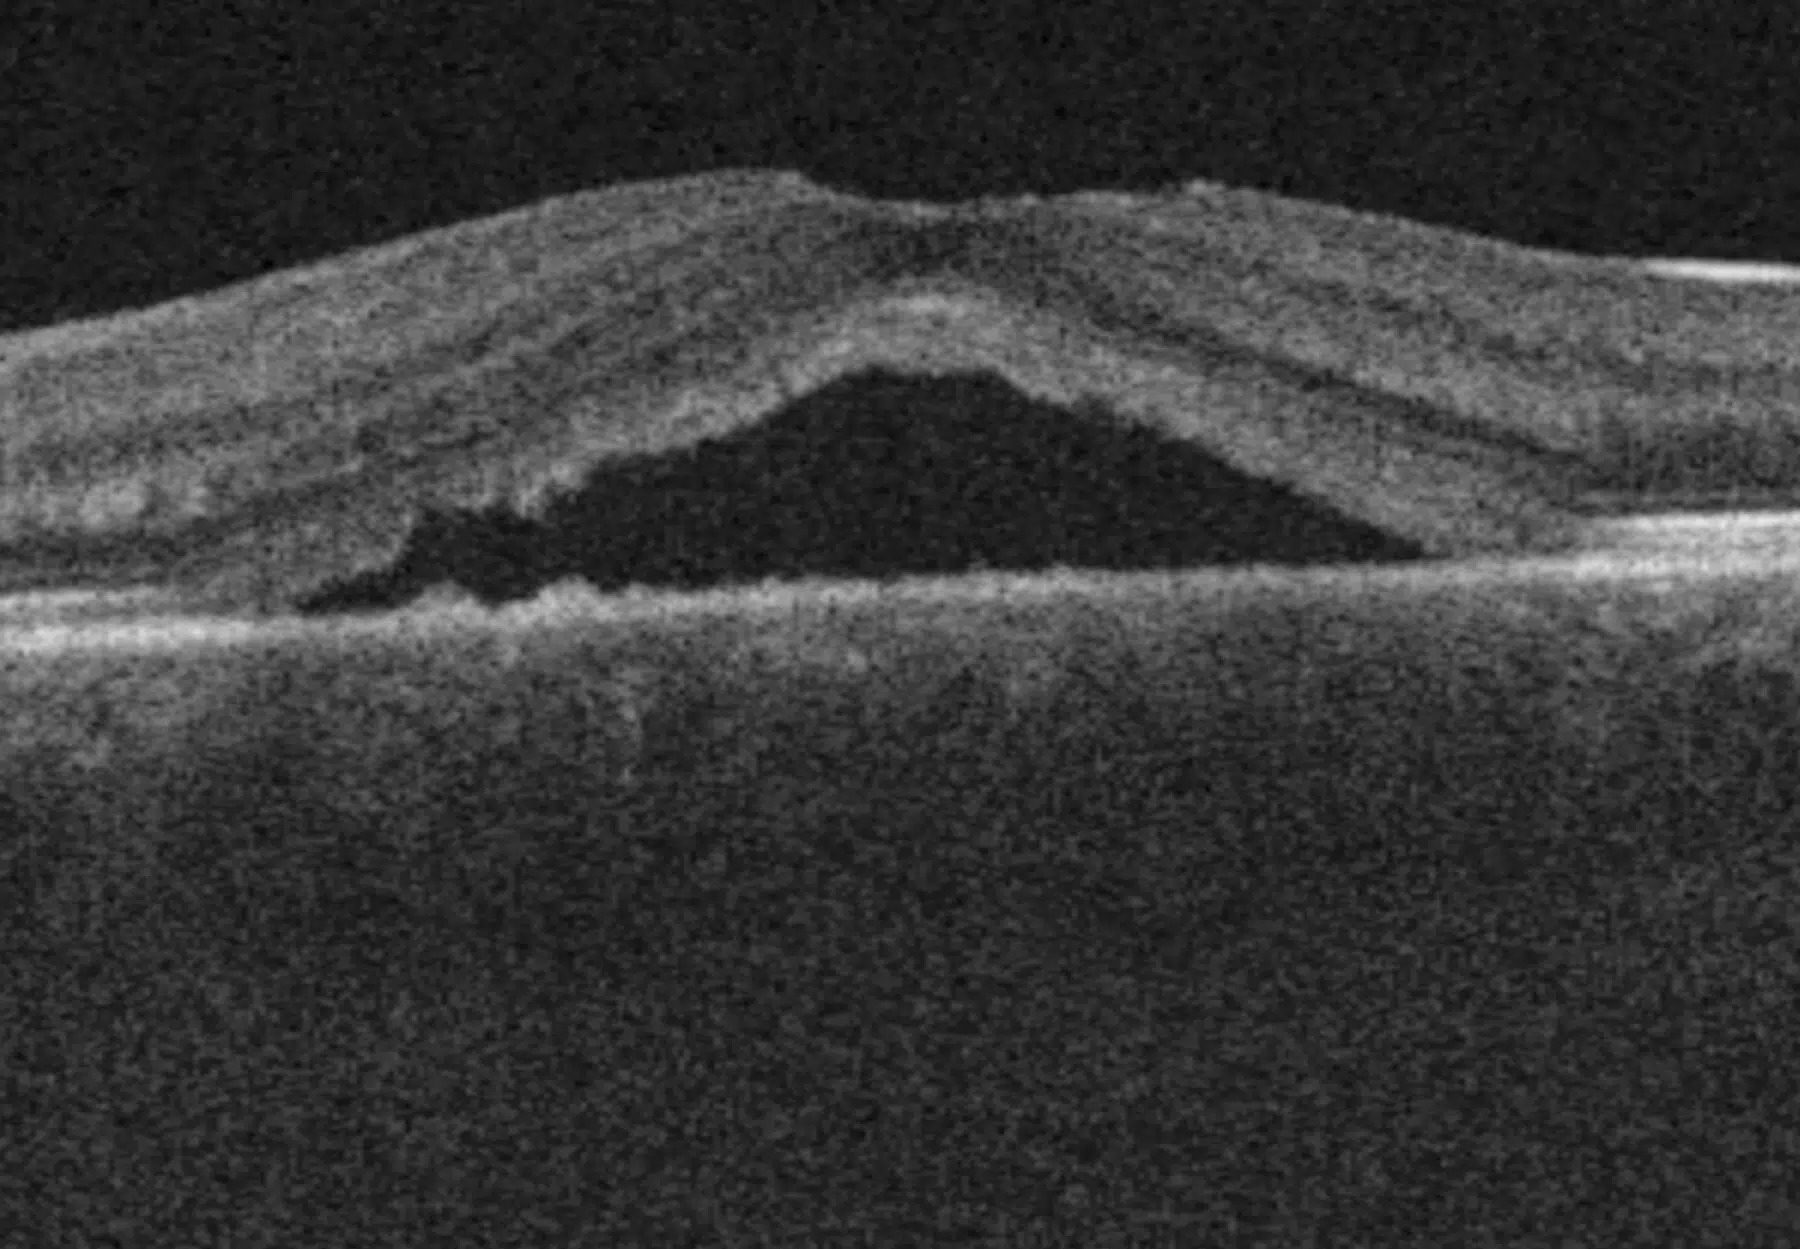

• OCT : un outil clé pour observer la structure rétinienne et évaluer la résolution ;

La choriorétinopathie séreuse centrale est causée par une fuite de liquide sous la rétine, à proximité de l’épithélium pigmentaire, provoquant un décollement localisé. Elle affecte le plus souvent la macula, zone responsable de la vision fine. Ses symptômes incluent une baisse de vision, des métamorphopsies (lignes ondulées), ou encore des zones sombres dans le champ de vision.